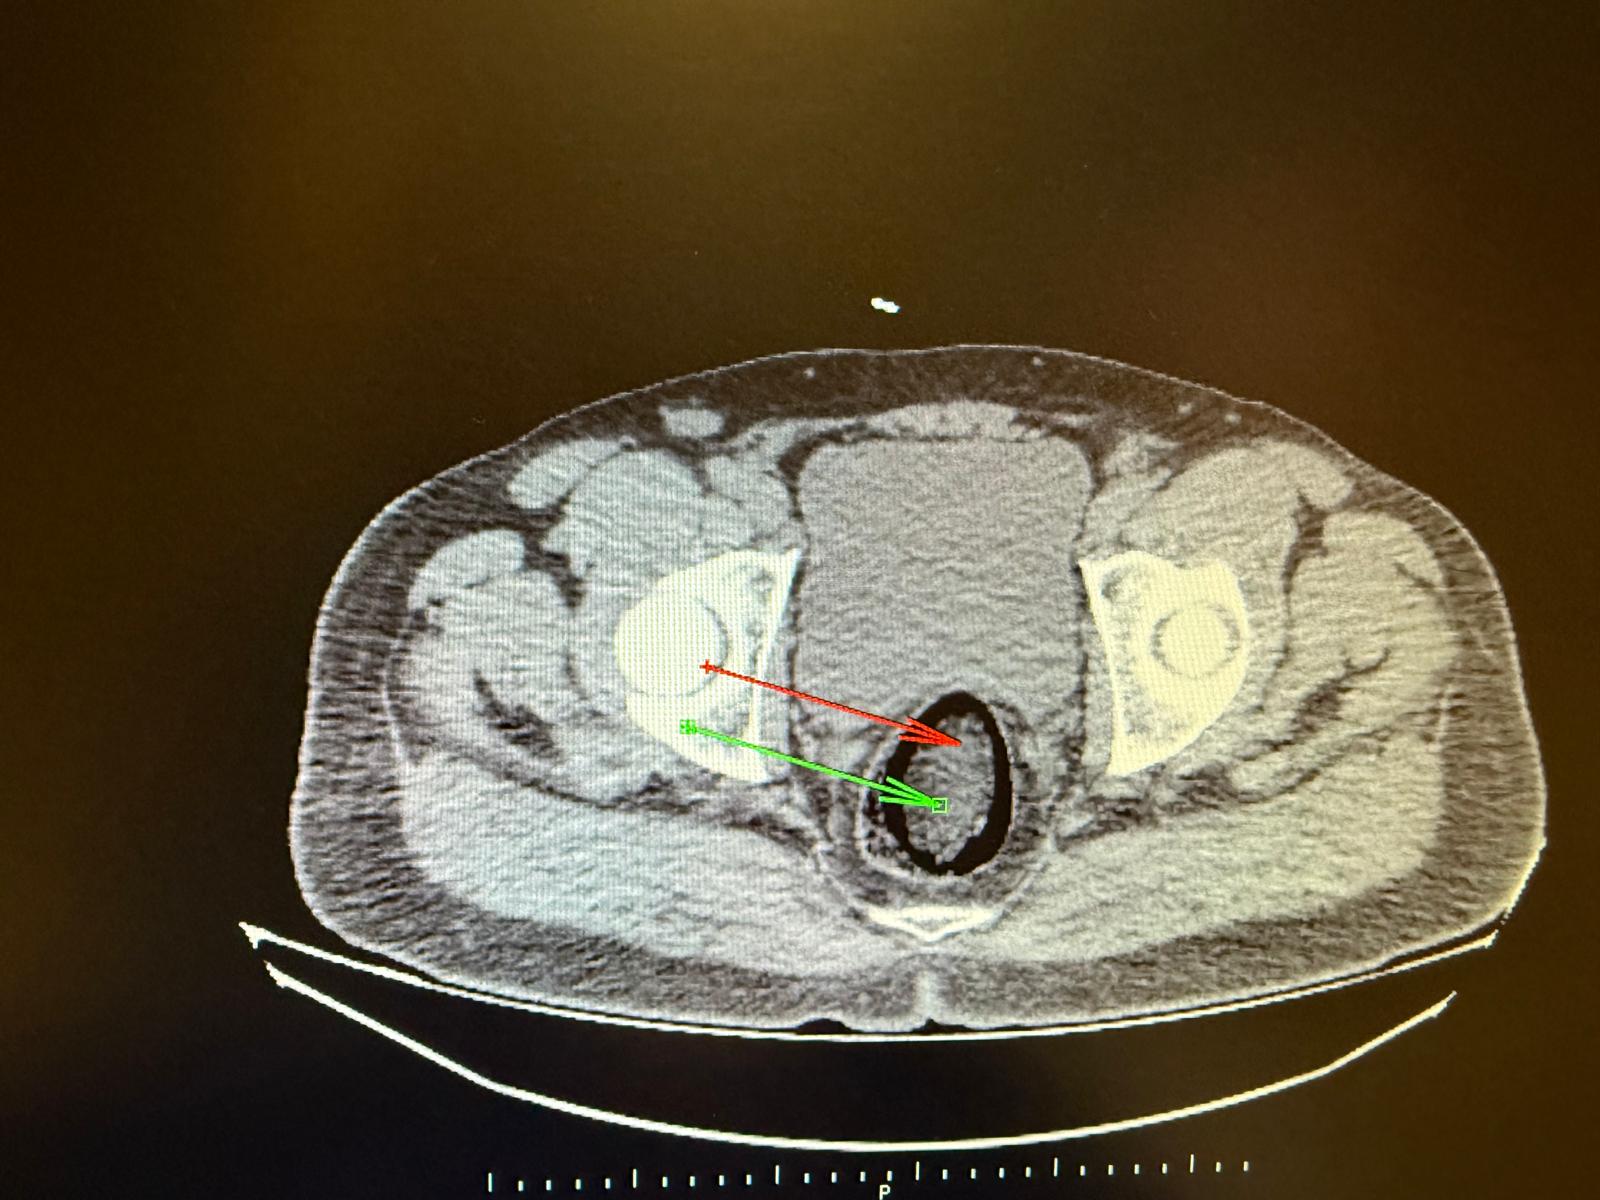

Kars Harakani Devlet Hastanesi'ne götürülen F.H.'nin çekilen röntgeninde, makatında uyuşturucu tespit edildi. Cerrahi operasyonla makatından 105,98 gram metamfetamin metamfetamin çıkarıldı. Emniyetteki işlemlerinin ardından adliyeye sevk edilen şüpheli, çıkarıldığı hakimlik tarafından tutuklandı.